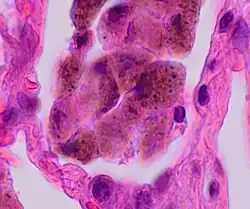

Micrograph showing hemosiderin-laden alveolar macrophages, as seen in a pulmonary hemorrhage. H&E stain.